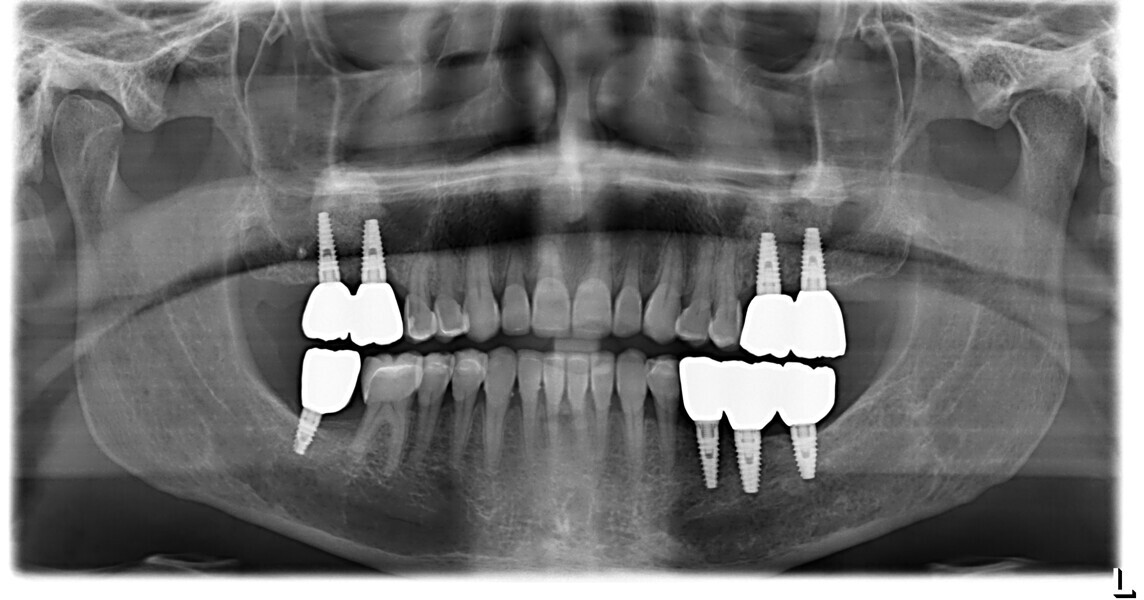

This patient, like all patients requiring interdisciplinary rehabilitation, had to first undergo periodontal treatment and caries restoration (Fig. 17). At the same time, it was important to rehabilitate swallowing with Froggymouth and relax the masticatory muscles and relieve the TMJs with an occlusal device. We could then study the orthodontic treatment plan using Invisalign ClinCheck (Align Technology) and showed the treatment plan to the interdisciplinary team and to the patient (Fig. 18). We were then able to create the correct sequence of orthodontic treatment, bone augmentation and implant surgery needed for the posterior edentulous spaces.

After the first phase of aligner treatment, we had achieved better inter-arch coherence, better maxillary arch expansion, and some space for improving the anterior tooth proportions restoratively (Fig. 19). We then temporarily restored the anterior teeth directly with composite, closing the spaces, improving the tooth proportions and further increasing the maxillary arch expansion (Fig. 20). We used restorative arch expansion to reduce the orthodontic destabilisation of the teeth to achieve the correct inter-arch coherence and retain the teeth in the cortical bone.38 A refinement aligner phase was undertaken to improve the final alignment of the gingival zenith and to improve the inter-arch coherence (Fig. 21). The periods of the first orthodontic phase and of the refinement were used to augment the mandibular and maxillary bone and to place the implants (Fig. 22). At the end of the orthodontic treatment, the case was finalised with ceramic veneers in the anterior area and temporary restorations on the implants in the posterior area (Figs. 23–26).

The provisional phase of about four months was important to allow the peri-implant tissue to mature and to teach the patient to chew correctly with chewing gum, cotton rolls and silicone masticatory sticks. This is fundamental training for the patient to achieve the correct alternating unilateral masticatory cycle needed to obtain the ideal rehabilitation of the masticatory system. We wanted the patient to achieve ideal masticatory and swallowing function. After sufficient rehabilitation time, we finalised the case with posterior zirconia crowns screwed on to the implants (Fig. 27).26